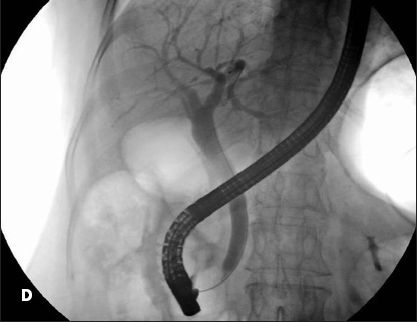

Surgery revealed a large common bile duct at the level of the confluence between the right and left ducts at the hepatic hilum; the gallbladder was absent. A postoperative endoscopic retrograde cholangiopancreatography showed a mildly dilated proximal bile duct of 10 mm that slowly tapered to 8 mm distally; the cystic duct and gallbladder did not fill (D). Based on these findings and the history of midepigastric pain, the diagnosis of type II sphincter of Oddi dysfunction was entertained and an endoscopic sphincterotomy was performed.